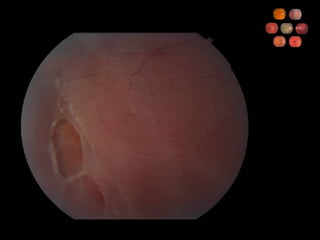

45 yo h/o HTN

Retinal Arterial Macroaneurysm What percentage of cases are associated with systemic hypertension? 67% What are causes of visual loss? Intra- or subretinal hemorrhage Vitreous hemorrhage Macular edema/exudation